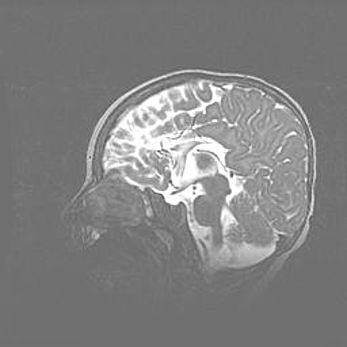

Аномалия Денди-Уокера. Признаки гипоплазии мозолистого тела.

Возраст: 5 месяцев 3 дня

Вес: 5550 г

Пол: мужской

Окружность головы: 39 см

Срок гестации: 40 недель

Аномалия Денди-Уокера – это порок развития головного мозга, для которого характерна триада симптомов: гипотрофия или аплазия червя мозжечка и/или полушарий мозжечка, расширение четвёртого желудочка с формированием ликворной кисты задней черепной ямки, гипертензионная гидроцефалия различной степени.

Гипоплазия мозолистого тела относится к дефектам внутриутробного этапа развития мозговой ткани, возникающим в процессе закладки структур головного мозга, что происходит на начальных этапах развития эмбриона.